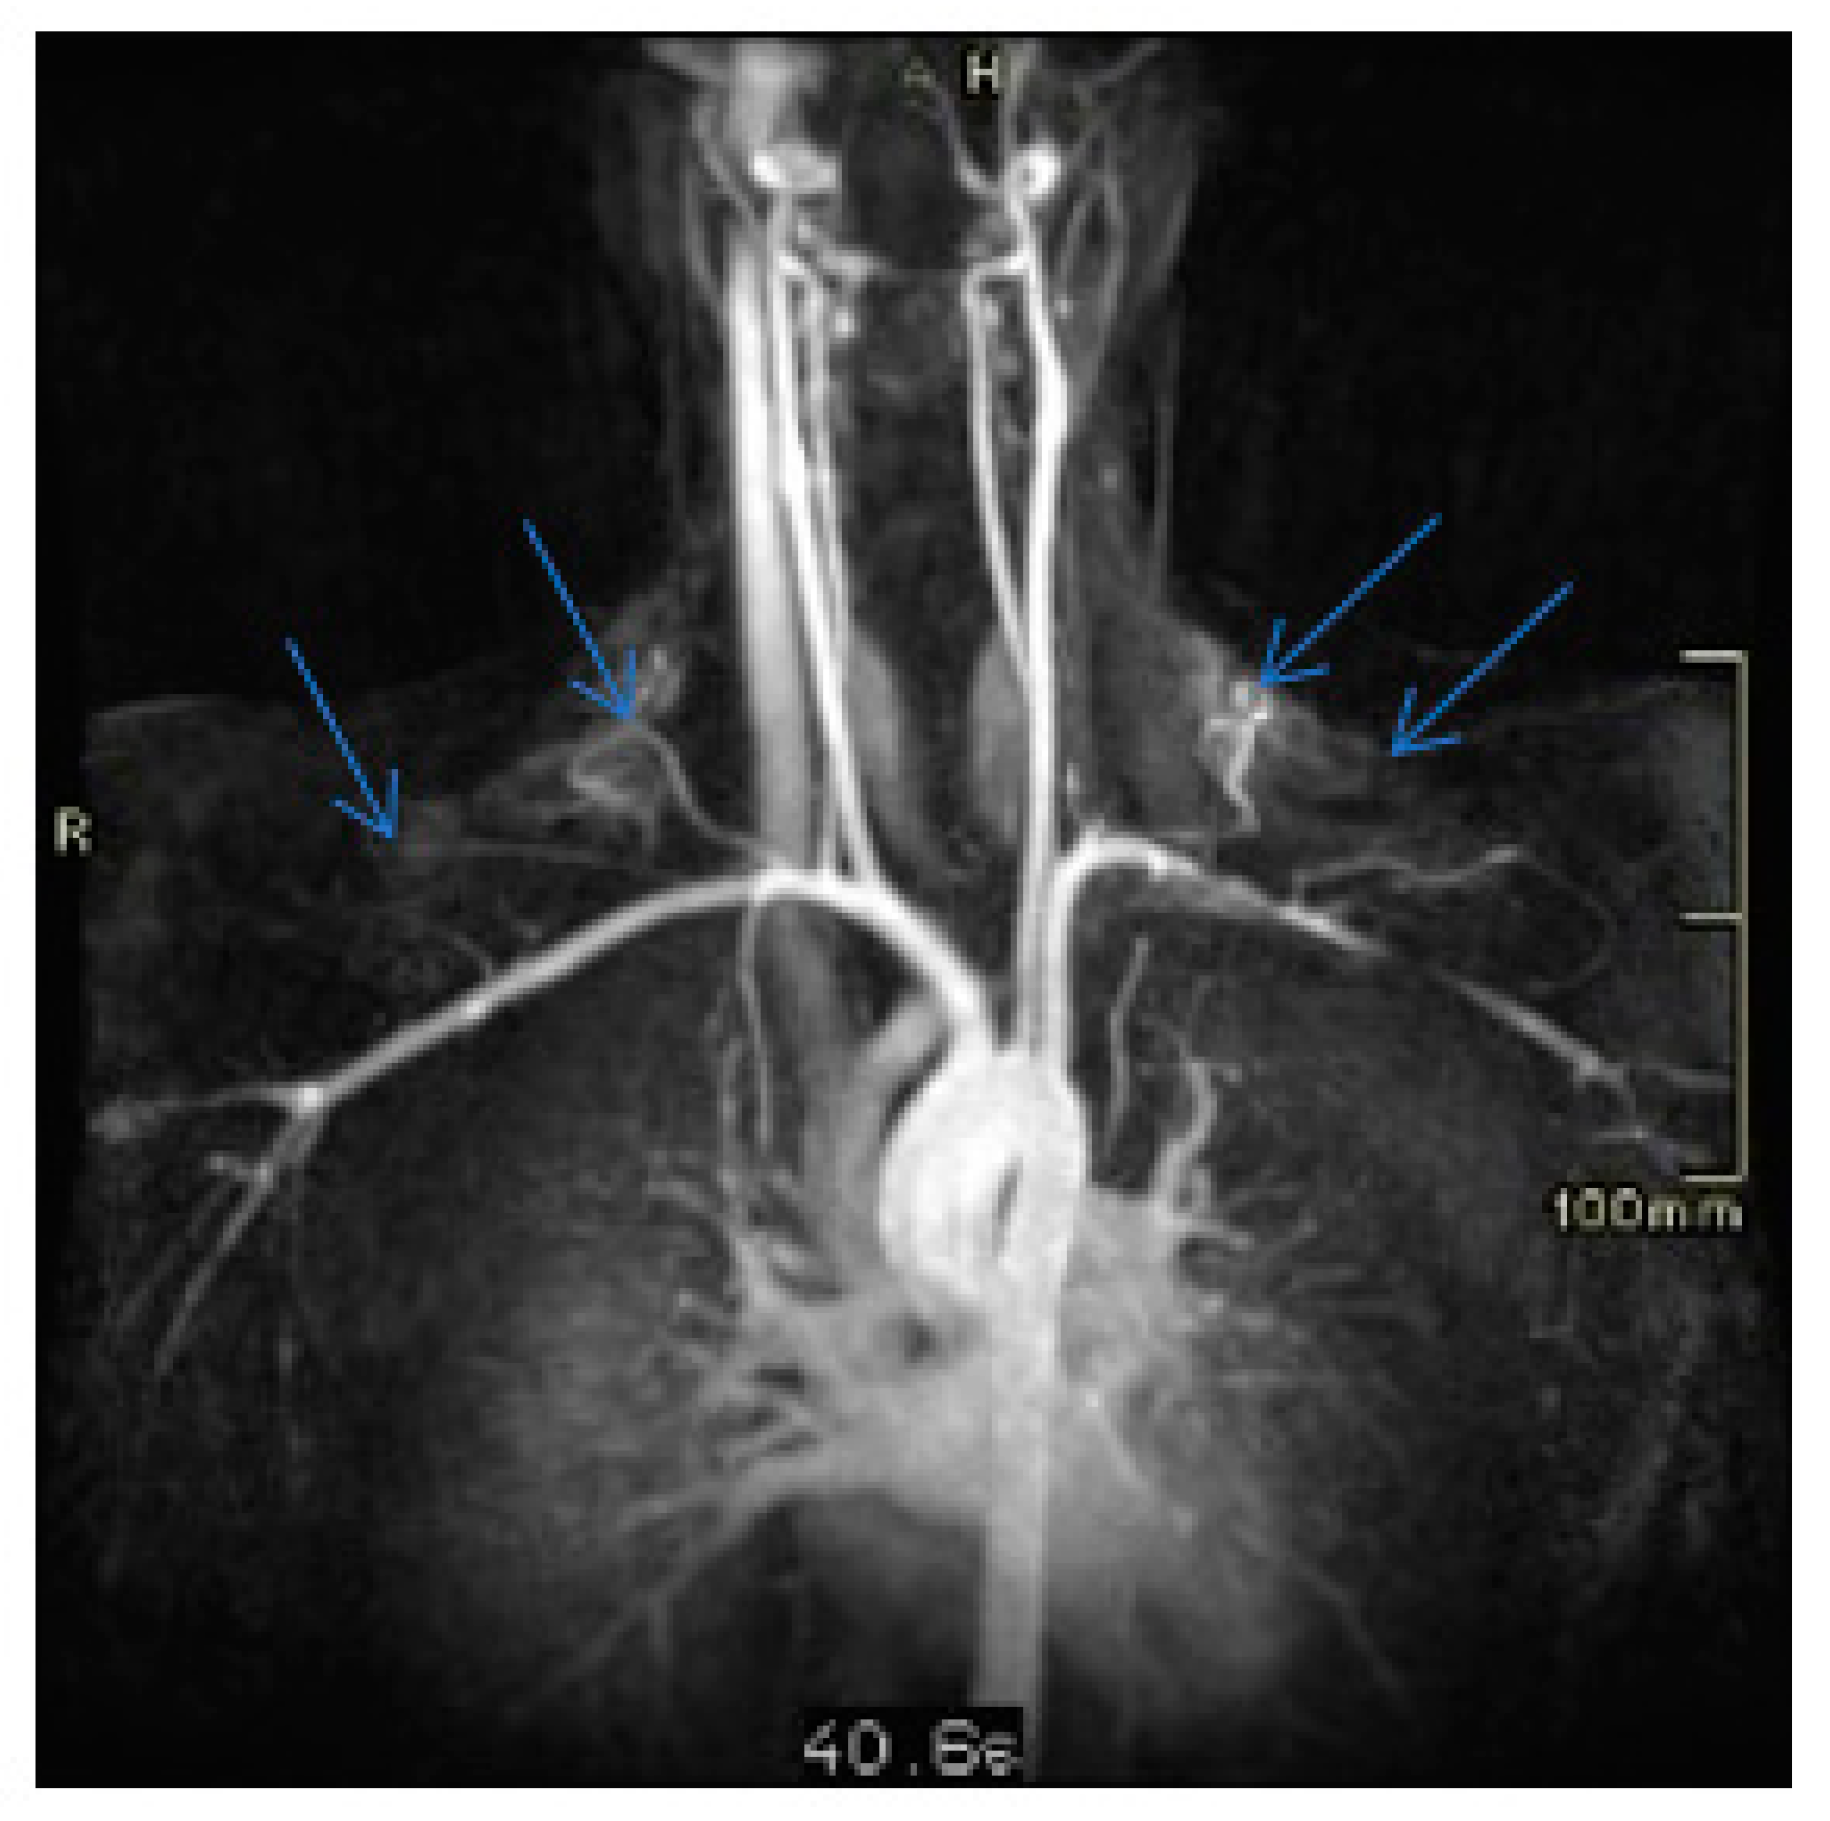

2. Case Presentation